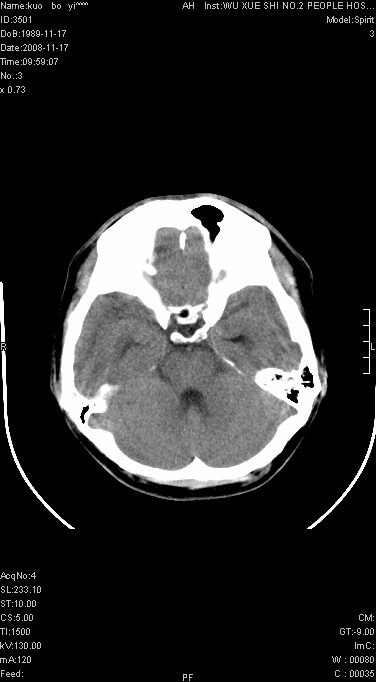

增强后水肿中心高密度灶有明显强化,强化不均匀,呈雪花状或絮状,且强化明显,若为肿瘤,应该出现形态较规则的瘤体影,强也有例外如胶质瘤就可以形态不规则.但胶质瘤明显强化者多为恶性间变性,与病史及相关表现太不相符.因此本例多考虑为炎症引起.

本例与重庆中华放射学年会读片大赛上第12个病例(由山东医影研究所柳澄教授提供)有异曲同工之妙(影像表现几乎相同).那个病例我的第一选择是炎症,其次是血管畸形,最后选项择的占位.但得到的答案是ms,新发的ms灶可见明显强化,但这么大的病灶着实没有想到,可能本例就影像表现来说也不能排除ms可能

患者年龄才19岁,病史很短,也较符合炎症等短程病变.

考虑左侧顶叶脑炎可能;建议追踪复查。

左顶叶较大范围水肿区,内见明显强化的片状 棉絮状组织,但占位效应不明显。多考虑:脑炎!

左顶叶大范围水肿,内见明显强化的片状 棉絮状组织,但占位效应不明显。考虑脑炎可能性大。